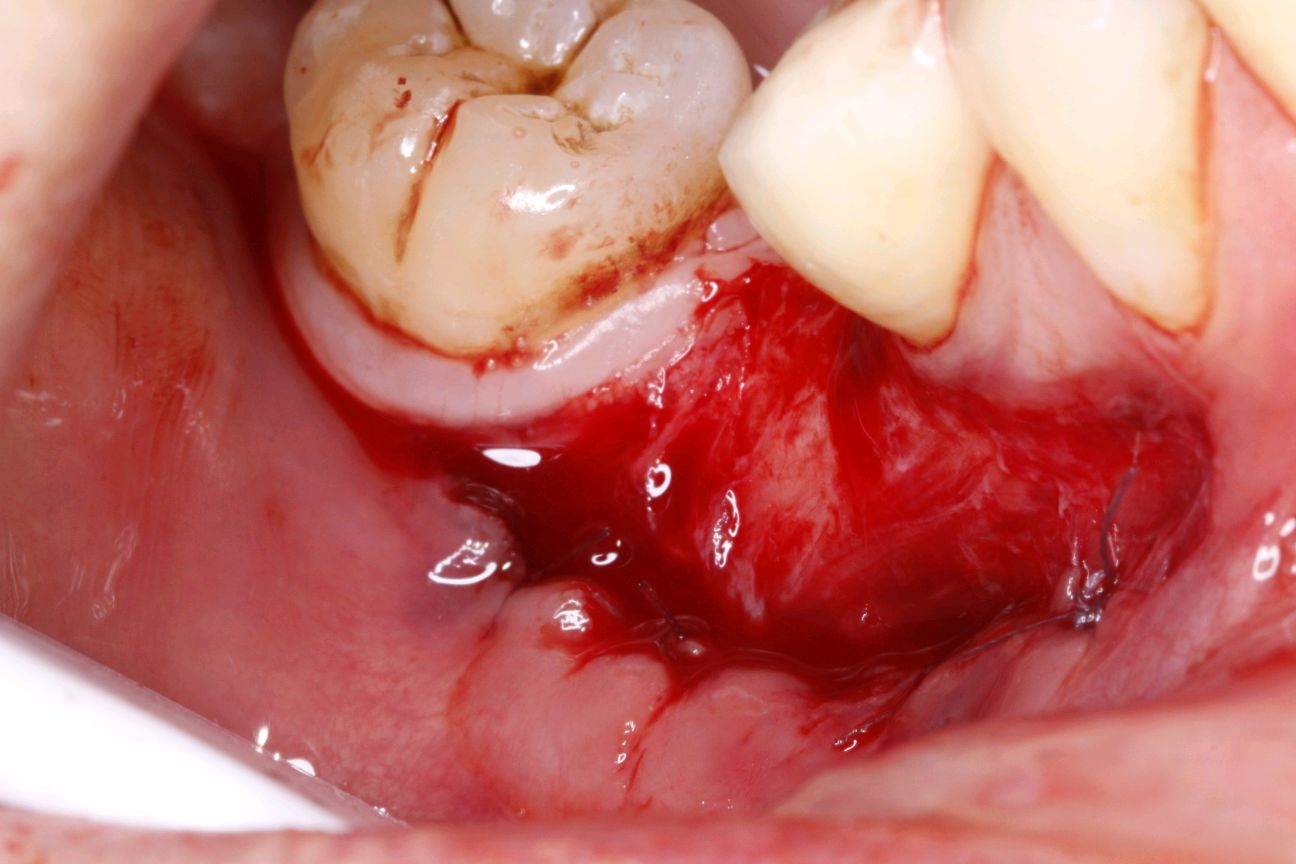

受区准备:15号刀片沿着膜龈联合联合部位做,深为1mm的水平切口,向根方组织充分锐性分离